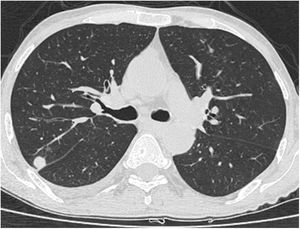

A relationship was identified between the pleura and one or more of the lesions in 25 of the 34 patients diagnosed with PAE (73.5%) (Fig. 1). Following the lesion-pleura relationship, multiple lesions were uniformly scattered throughout the bilateral lung parenchyma in 19 patients (55.8%), seven patients (20.6%) presented with a solitary pulmonary lesion and three patients (8.8%) had multiple unilateral lesions. The diameter of one or more lesions was greater than 3cm in 11 patients (32.4%), only three patients (8.8%) had conglomerated lesions (Fig. 2) and seven patients (20.6%) showed cavitization in some of the lesions. The majority of cavitary mass measured greater than 3cm (Fig. 3). Calcified lesions were recorded in five patients (14.7%), and some of the calcified lesions with lobulated contours had a typical popcorn appearance. Lobulated contours were observed in a significant proportion of non-calcified lesions. Some of the lesions had irregular contours and spicular extensions mimicking malignant processes in five patients (14.7%), while three patients (8.8%) showed multiple micronodular densities with a bilateral uniform dispersion pattern (Fig. 4). The appearance of pulmonary involvement resembled miliary tuberculosis. Parenchymal lesions were accompanied by pleural effusion and parenchymal consolidation in only three patients (8.8%) (Table 1).

Axial thoracic CT scan with lung parenchyma window of a 74-year-old male patient showing multiple lesions in the bilateral lung parenchyma. Some of the lesions show a tendency to cavitization and some show a tendency to conglomeration. Parenchymal lesions tend to have peri-pleural localization in the lung periphery. The patient has been followed for 6 years due to PAE.